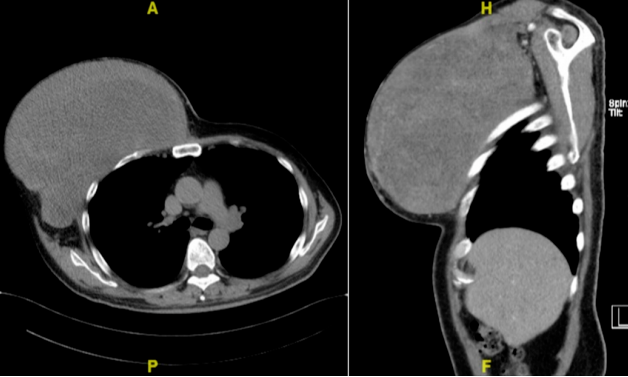

▲李先生术前胸部CT

58岁的李大爷,曾以手术方式切除鸡蛋大小的胸壁肿瘤,术后病理为增生性肌炎。肿瘤迅速复发并不断增大,成为长在右前外侧胸壁近腋窝处的巨大肿瘤,让患者的右上肢活动受到了严重影响。

李大爷来到北京协和医院胸外科门诊,经过细致问诊,李单青主任认为,肿瘤可能不单纯是增生性肌炎,应该尽快手术。考虑到肿瘤被切除后,患者胸壁将出现巨大缺损,胸壁完整性及呼吸功能均会受到影响,为此,李单青主任、黄诚副主任医师、郭超主治医师同整形美容外科张海林副主任医师、张文超医师在术前为李大爷量身定制了一套完备的手术方案。